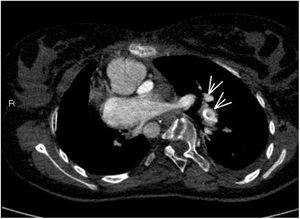

Niña de 16 años con antecedentes personales de cardiopatía congénita compleja que precisa fístula sistémico-pulmonar derecha, y a los 6 años de edad anastomosis cavo pulmonar bilateral (intervención de Glenn). Ingresa en la UCI pediátrica por dificultad respiratoria e hipoxemia severa. Ante la sospecha de TEP se inicia tratamiento con heparina sódica y 24h más tarde por empeoramiento clínico progresivo se realiza nuevo angio-TAC, donde se visualiza trombo en la comunicación de VCSI con arteria pulmonar izquierda compatible con tromboembolismo masivo de pulmón izquierdo (fig. 1, ver flechas). Se inicia tratamiento con activador recombinante tisular del plasminógeno (rTPA), bolo inicial de 30mg (0,5mg/kg), seguido de perfusión de 0,04mg/kg/h. A las 36h en nuevo angio-TAC de control se evidencia una importante disminución de los trombos con notable repermeabilización (fig. 2, ver flechas).